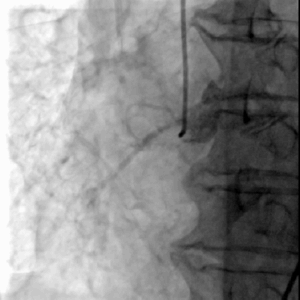

冠脉造影

LAD可见:近段70%-80%弥漫性狭窄,远段75%局限性狭窄,向右冠发出极丰富倒枝循环

LCX远段闭塞

右冠中段闭塞

冠脉造影提示患者存在严重冠脉病变,结合病史,缺血性心肌病诊断明确;

CAG后即刻出现血压下降、心率增快,考虑循环崩溃,因此需立即解决重度主动脉瓣狭窄